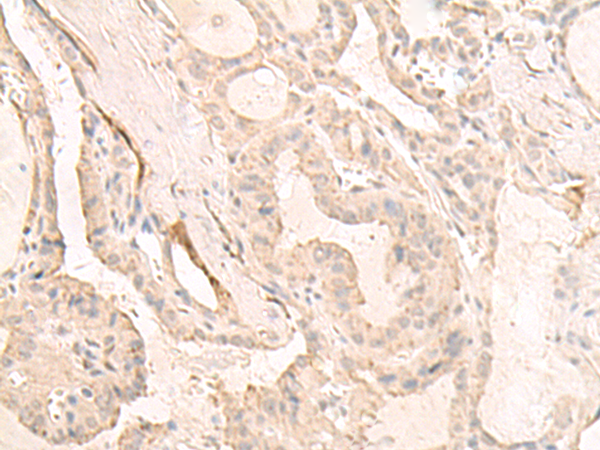

IHC positive control: |

Human thyroid cancer |